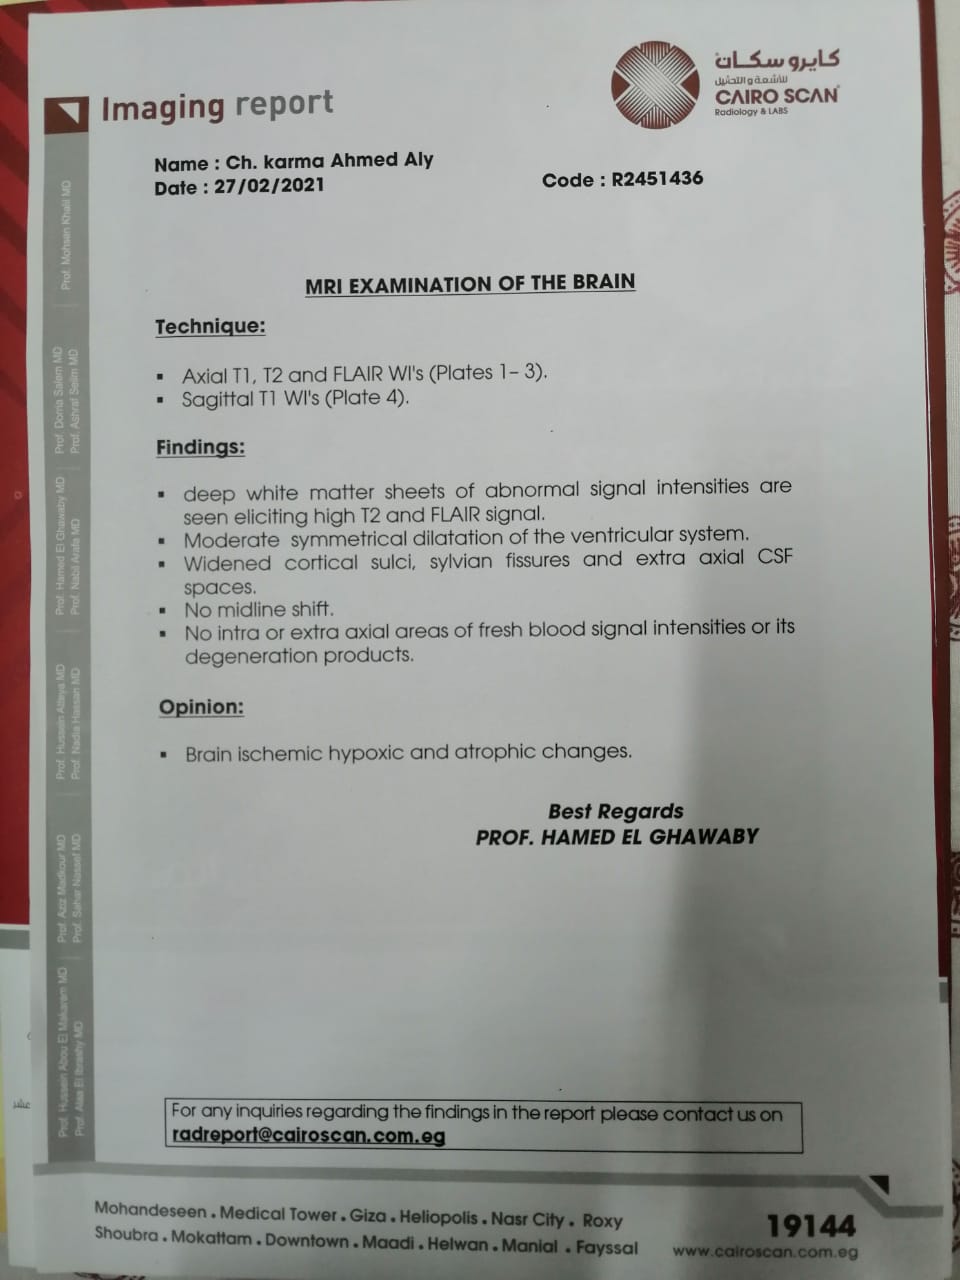

وأشار إلى أنه بعد خروج كارما من المستشفى تم إجراء فحوصات أخرى عليها، تبينت عدم التطابق بين التقارير الطبية لها بداخل المستشفى والفحوصات الجديدة.

وقال علي: "بنتي جالها ضمور في المخ وفي كل الحواس، بسبب الدوا الغلط، بنعملها علاج طبيعي بيتكلف في الشهر 20 ألف جنيه"، مشددًا": "هي بتفتح عينها بس".